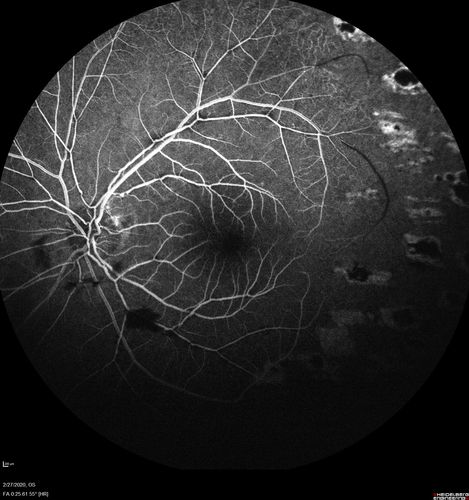

Eales Disease and fresh vitreous hemorrhage - 20 year old man

20 year old mane with fresh vitreous hemorrhage in the right eye.  At age 15 he had a PPV and laser in the left eye and laser in the right eye.  The vision is OD 20/80 PH 20/25, OS 20/25.  The left eye has a mild cataract.  He had prior testing for coagulopathies which was negative.  Testing done for syphillis and TB was negative.  Additional laser was done to prevent further bleeding in the right eye.